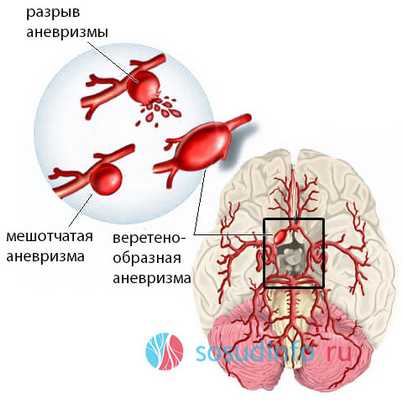

Снимки и иллюстрации микроаневризм сосудов головного мозга